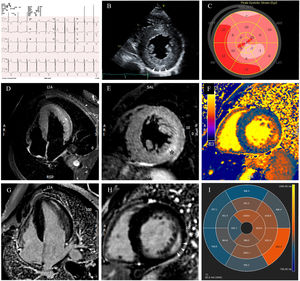

Un varón de 49 años fue remitido al servicio de urgencias para evaluación por dolor torácico atípico y palpitaciones. En el electrocardiograma (figura 1A) destacaba un intervalo PR corto, con signos de hipertrofia ventricular izquierda. Dado que la troponina estaba ligeramente elevada, se hizo una coronariografía invasiva, que fue negativa para enfermedad coronaria. La ecocardiografía transtorácica (figura 1B; ) confirmó la hipertrofia ventricular izquierda con fracción de eyección conservada, músculos papilares prominentes y aumento de la ecogenicidad de la pared inferolateral (puntas de flecha). El estudio de la deformación reveló una reducción del strain longitudinal global (−13,2%), con afección regional, principalmente en la evaluación de la capa epicárdica en el análisis del strain circunferencial (figura 1C; ). La cardiorresonancia magnética () mostró un edema extenso (asterisco) tanto en la pared lateral como en la inferolateral (figura 1D,E; STIR: recuperación de inversión tau corta) con realce tardío de gadolinio intramural concomitante (figura 1G,H, puntas de flecha). En el mapeo miocárdico destacaban los valores de T1 anormalmente bajos excepto para las paredes laterales, en las que eran anormalmente altos (intervalo normal: 972-1.070ms) (figura 1F,I). Esto condujo a la hipótesis de que se tratara de la enfermedad de Fabry, que después se confirmó por el aumento de las concentraciones séricas de globotriaosilesfingosina (liso-Gb3) y la presencia de una variante patogénica en GLA: c.902G>A, p.(Arg301Gln). En un estudio diagnóstico más detallado se descartaron afecciones renal y neurológica, angioqueratomas o deterioro visual y se identificó a 1 hermano y 2 primos con la enfermedad (figura 2, árbol genealógico). Se propuso un tratamiento específico de chaperona con migalastat.

A pesar de las características clínicas y las exploraciones de imagen típicas que respaldaban el diagnóstico de miocardiopatía de Fabry, en este caso destacan las alteraciones tisulares específicas. Los valores de T1 seudonormalizados y superiores a los normales, que corresponden a cambios como los derivados de la inflamación y la fibrosis, pueden ocurrir en distintas etapas de la enfermedad y con eventos clínicos y liberación de troponina. El análisis de la deformación (strain) de la función regional se corresponde con la caracterización tisular.